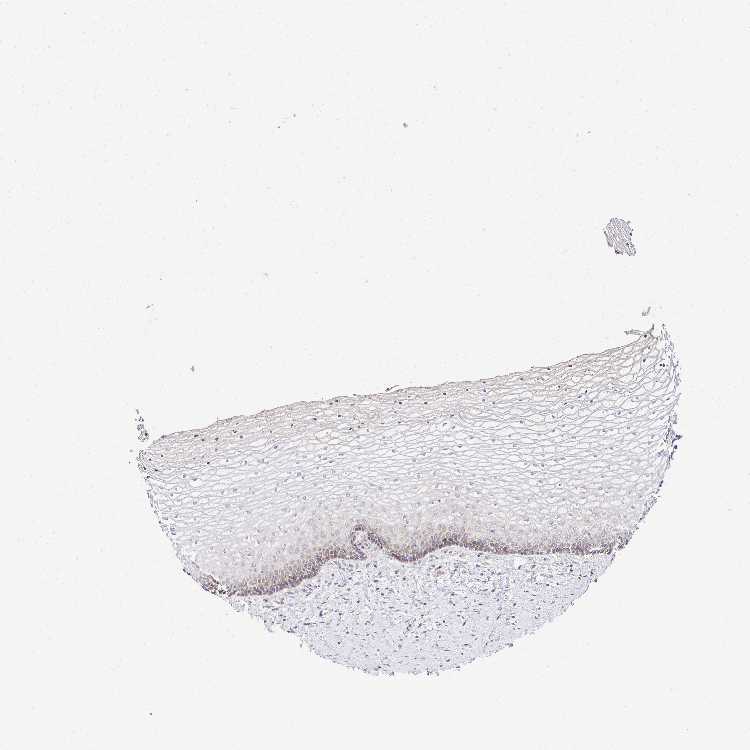

VAGINA - Antibody stainingi

Antibody staining in the annotated cell types in the current human tissue is reported as not detected, low, medium, or high, based on conventional immunohistochemistry profiling in selected tissues. This score is based on the combination of the staining intensity and fraction of stained cells.

Each image is clickable and will lead to virtual microscopy that enables deeper exploration of all samples and also displays staining intensity scores, fraction scores and subcellular localization as well as patient and tissue information for each sample.

Antibody HPA060899

Squamous epithelial cells Medium